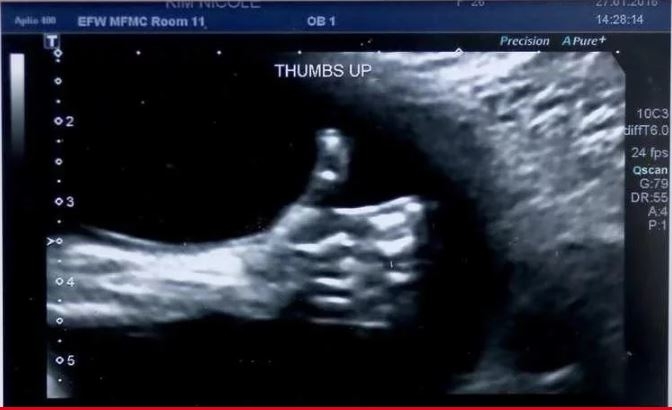

El bebé "me gusta"

Nicole Kim, una madre canadiense, recibió un gran gesto de su tercer hijo, directamente desde la panza y antes de nacer: un pulgar arriba.

Nicole y su marido se pusieron contentos al ver el gesto del bebé y lo tomaron como una señal de que todo va a salir bien. Ella compartió la imagen en las redes y la hizo viral.